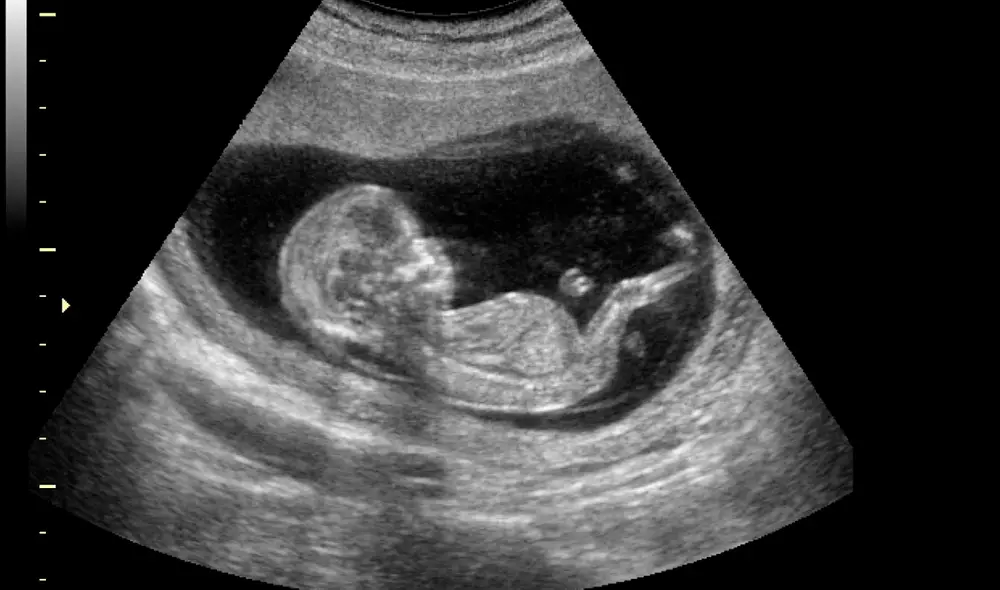

En Barranquilla, Colombia, se presentó un caso médico excepcional protagonizado por Mónica Vega y su hija Itzamara. Durante un examen ecográfico de rutina, se descubrió un fenómeno extremadamente raro: un feto alojado en el abdomen de la recién nacida.

Este fenómeno es conocido como fetus in fetu y ocurre en aproximadamente uno de cada 500.000 nacimientos, de acuerdo con los expertos en medicina materno-fetal.

El fetus in fetu es una extraña condición en la que un gemelo se desarrolla dentro del cuerpo de su hermano en lugar de hacerlo en el útero materno. Según el cirujano Miguel Parra, quien descubrió el segundo organismo en el cuerpo de Itzamara, esta condición ocurre cuando el embrión que debería dividirse para formar gemelos no se separa en el momento correcto.

Si la división ocurre en la primera semana, se forman gemelos; si ocurre en la segunda semana, pueden desarrollarse hermanos siameses. Sin embargo, en casos extremadamente raros como este, la división se produce después del día 17, lo que resulta en que un gemelo se desarrolle dentro del otro.

Durante el embarazo de Mónica, Itzamara se desarrolló normalmente gracias a la placenta y el cordón umbilical que la mantenían conectada a su madre. No obstante, el feto 'parásito' que crecía dentro de ella dependía completamente de su hermana para sobrevivir. Este gemelo carecía de placenta, corazón y cerebro, y utilizaba el corazón de Itzamara para bombear sangre y recibir los nutrientes necesarios.